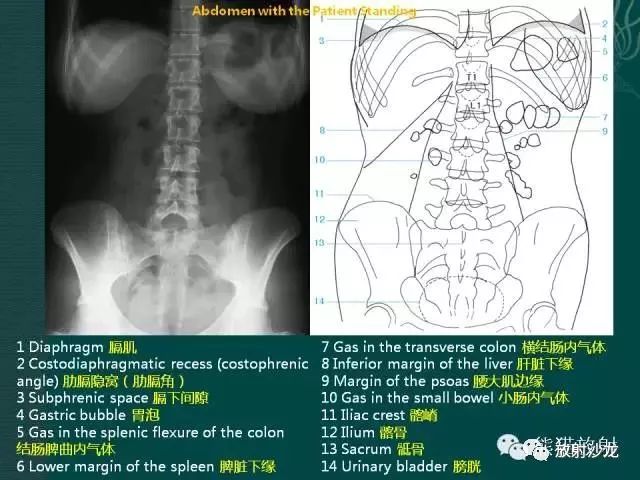

腹部脏器有实质器官和空腔脏器之分,其正常腹平片表现不同。

● 腹平片上实质器官的正常表现:

实质器官:肝、胰、脾和肾等是中等密度,但借助于器官周围或邻近的脂肪组织和相邻充气肠胃的对比,于腹平片上,可显示器官的轮廓、大小、形状及位置。

正位片在部分病人可显示肝下缘,肝下缘与肝外缘相交形成肝角,一般呈锐角。

脾上极与左膈影融合,下极较圆钝。而肾沿腰大肌上部排列。

胰腺于平片上不易显示。子宫偶尔显影,位于膀胱上缘上方呈扁圆形软组织影。

● 空腔脏器在腹平片上的主要表现:

空腔器官:膀胱的脏壁为中、胆囊和肠胃道等密度,依腔内容物不同而x线表现不同。

胃、十二指肠球部及结肠内可含气体,于腹平片上可显示其内腔。小肠除婴幼儿可有积气外,一般充满食糜及消化液,与肠壁同属中等密度,因缺乏对比而不能显示。

如胃内有较多固态食物,结肠或直肠内有较多粪便,由于它们周围有气体衬托,故可显出软组织密度斑片或团块影。

结肠分布于腹部四周。膀胱和胆囊周围有较多脂肪,也可显示部分边缘。